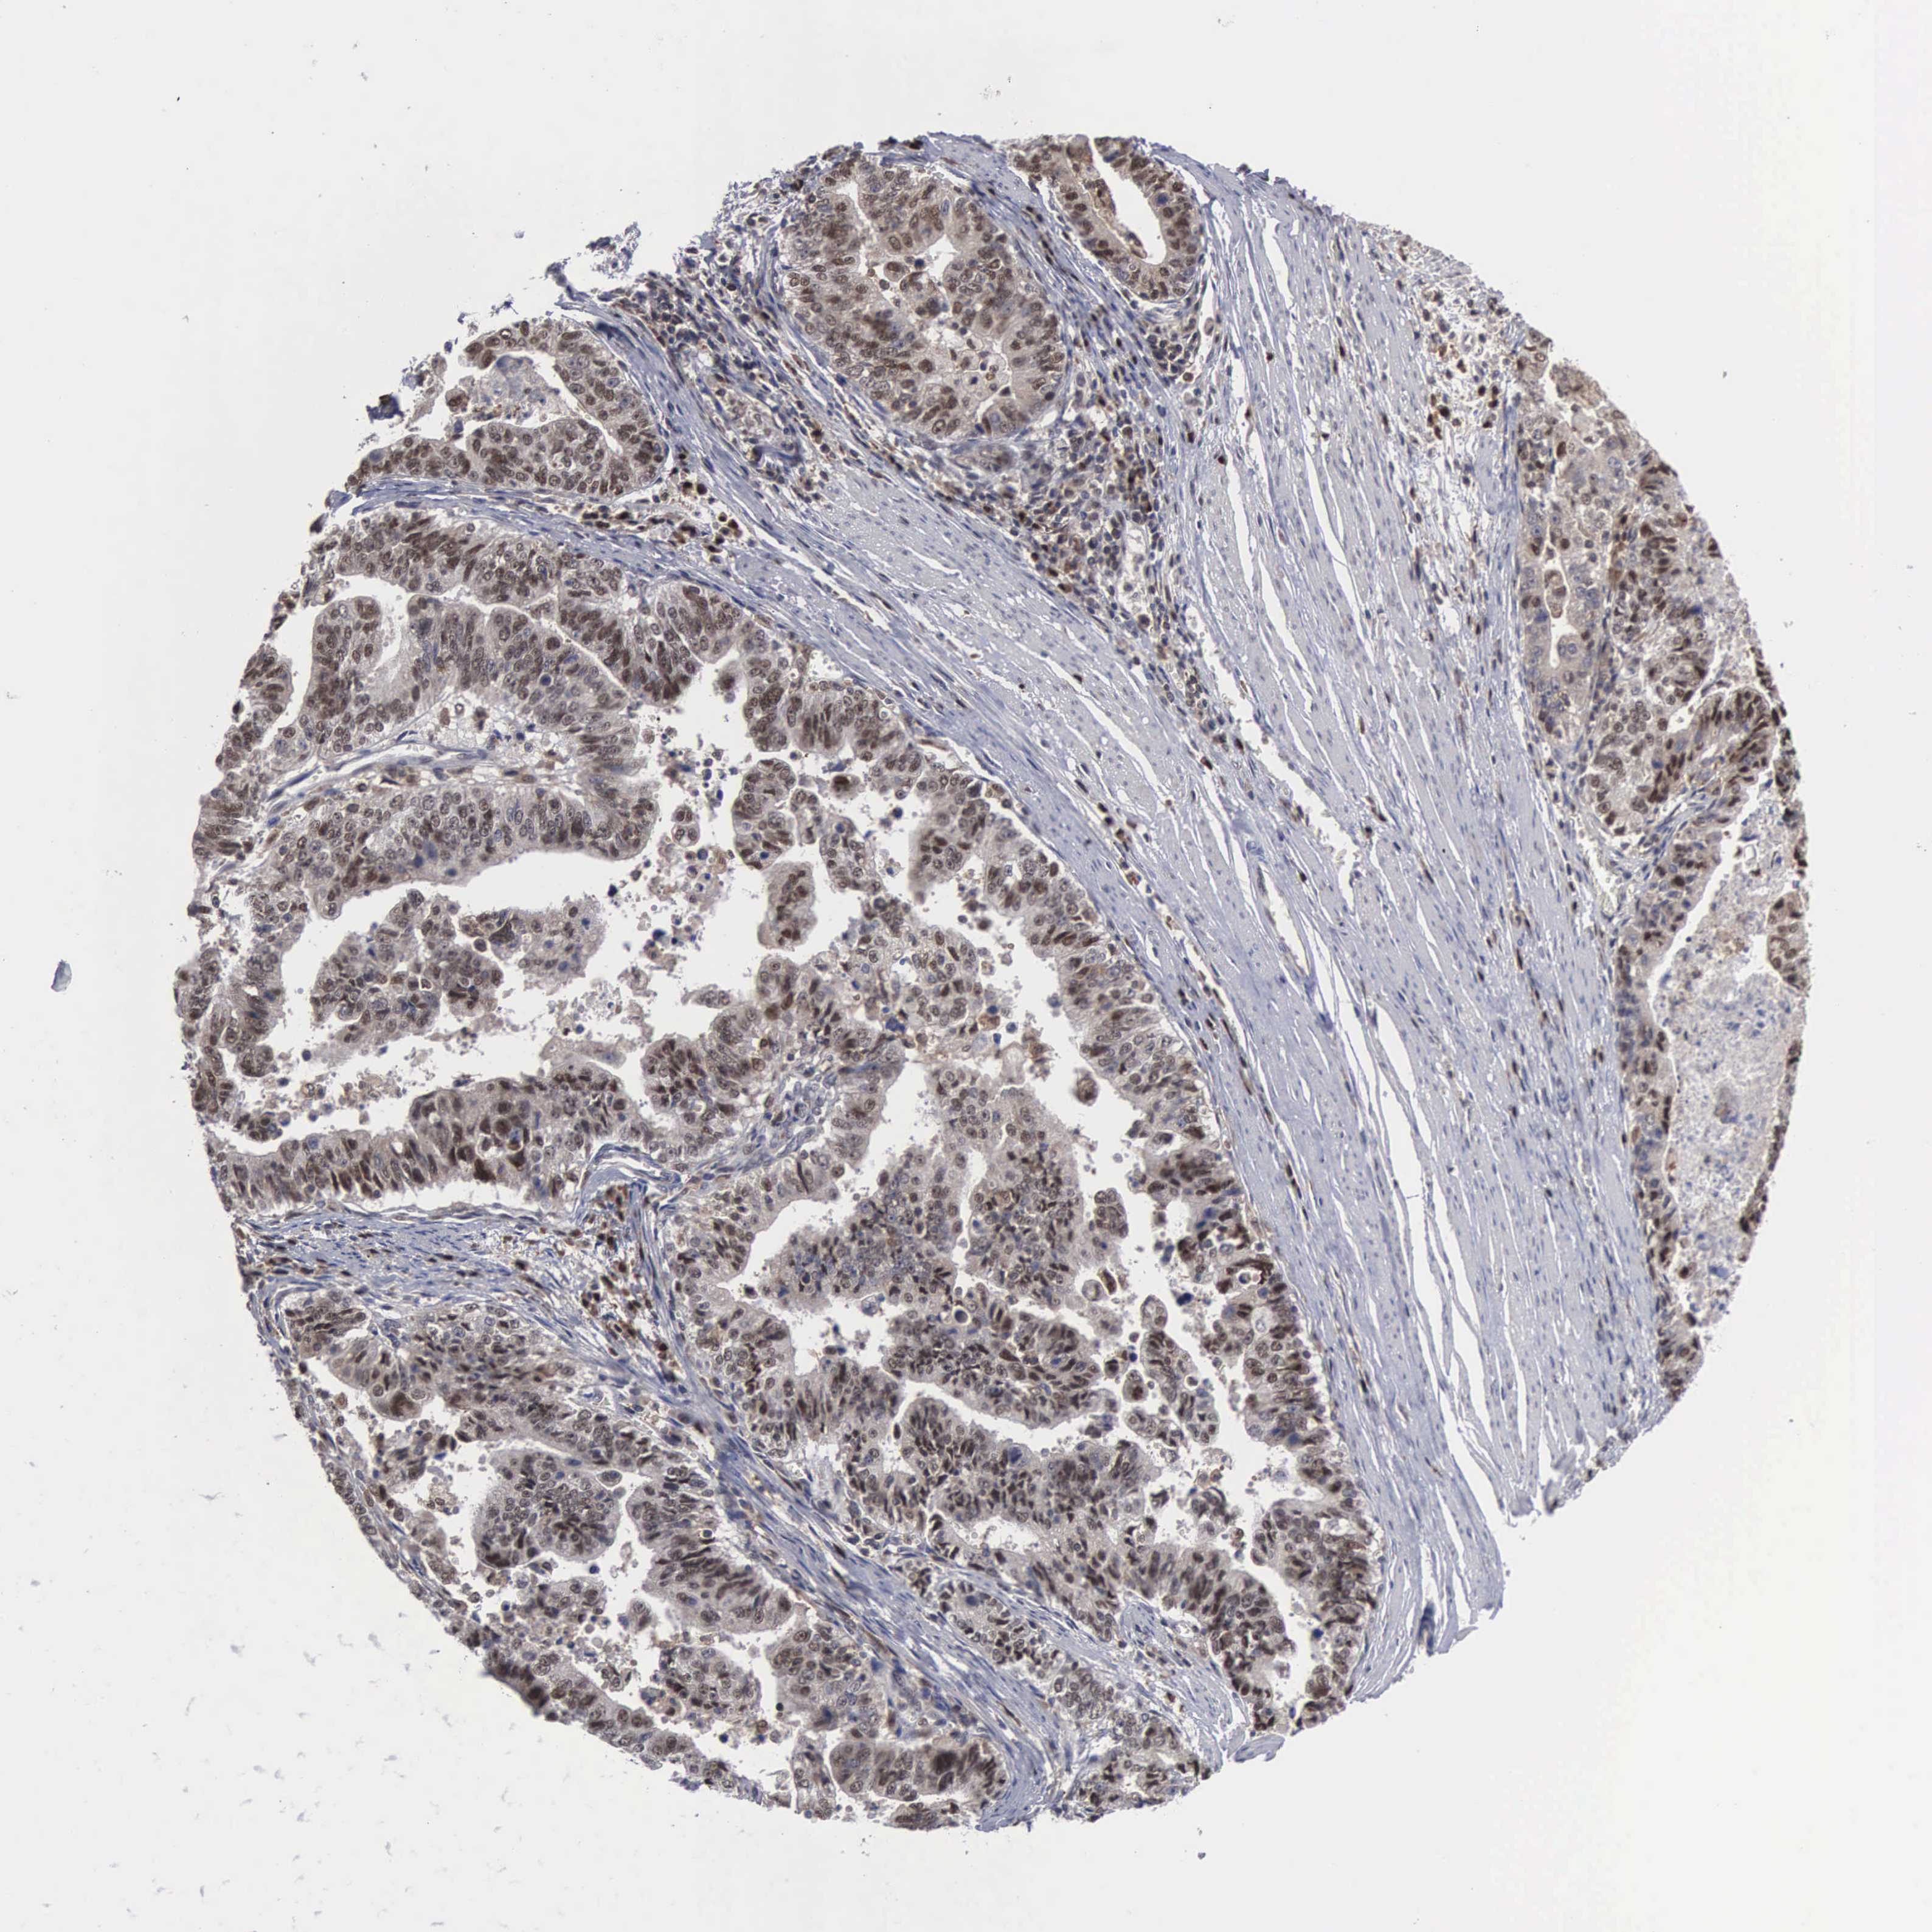

STOMACH CANCER - Protein expressioni

A mouse-over function shows sample information and annotation data. Click on an image to view it in a full screen mode. Samples can be filtered based on level of antibody staining by selecting one or several of the following categories: high, medium, low and not detected. The assay and annotation is described here.

Note that samples used for immunohistochemistry by the Human Protein Atlas do not correspond to samples in the TCGA dataset.

Antibody stainingi

Antibody staining in the annotated cell types in the current human tissue is reported as not detected, low, medium, or high, based on conventional immunohistochemistry profiling in selected tissues. This score is based on the combination of the staining intensity and fraction of stained cells.

Each image is clickable and will lead to virtual microscopy that enables deeper exploration of all samples and also displays staining intensity scores, fraction scores and subcellular localization as well as patient and tissue information for each sample.

Antibody HPA000943

Staining

High

Medium

Low

Not detected

Intensity

Strong

Moderate

Weak

Negative

Quantity

>75%

75%-25%

<25%

None

Location

Nuclear

Cytoplasmic/membranous

Cytoplasmic/membranous,nuclear

Adenocarcinoma, NOS